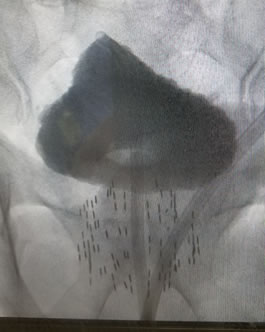

Implant completed in under one hour. |

Brachytherapy is an outpatient procedure and takes an hour or less when performed by an experienced team. Nearly ALL patients go home 3-4 hours later without a catheter and resume normal activities the next day or two. Since there is no incision and only a short anesthetic, treatment delivery is much better tolerated than surgery. Side effects do occur but are acceptable and generally disappear within months. Follow-up consists of PSA testing only twice a year for 4-5 years, then annually thereafter. Repeat biopsy or other invasive studies are not generally required.